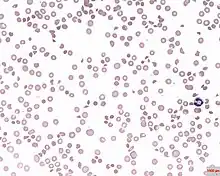

| A photomicrograph of the blood showing thrombocytopenia | |